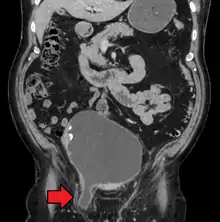

An incarcerated inguinal hernia as seen on cross sectional CT scan

A frontal view of an incarcerated inguinal hernia (on the patient's left side) with dilated loops of bowel above.